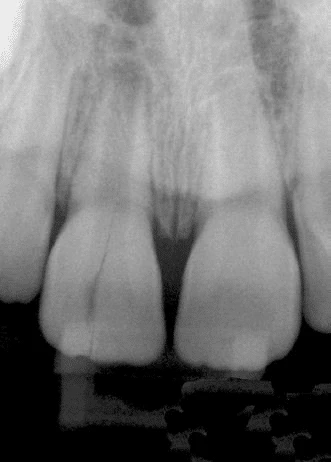

- Hình 14. Tiêu xương rộng khu trú quanh một răng, những răng cạnh đó bình thường, gợi ý một trường hợp nứt dọc chân răng

Hình 15. Khi răng có ống tuỷ rộng hơn so với răng cùng loại hoặc so với răng cạnh nó thì nên nghi ngờ có nứt dọc chân răng